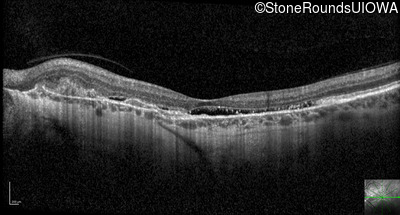

Optical Coherence Tomography - Right - 20/40

Exemplar / OCT Stack

OCT Stack